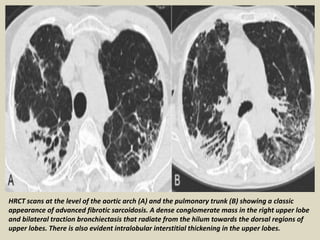

HRCT scans at the level of the aortic arch (A) and the pulmonary trunk (B) showing a classic

appearance of advanced fibrotic sarcoidosis. A dense conglomerate mass in the right upper lobe

and bilateral traction bronchiectasis that radiate from the hilum towards the dorsal regions of

upper lobes. There is also evident intralobular interstitial thickening in the upper lobes.